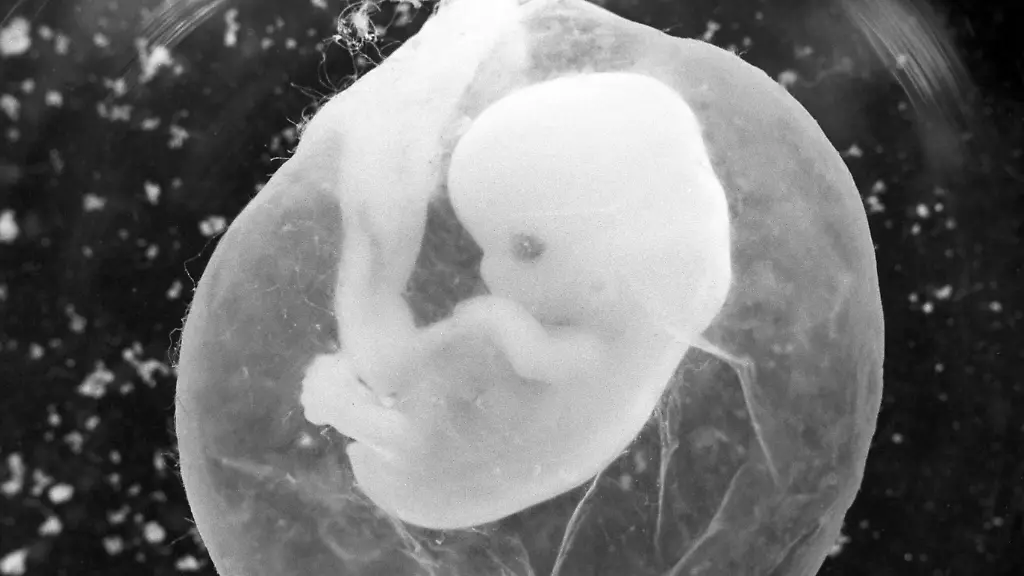

Ein chinesisches Forscherteam macht den Anfang, nun plant auch ein russischer Wissenschaftler, Embryonen mit einer genetischen HIV-Immunität zu erschaffen. Diesmal soll das Verfahren noch sicherer und ethisch vertretbarer sein, verspricht der Wissenschaftler. Trotzdem hat die Fachwelt große Bedenken.

Der russische Forscher Denis Rebrikow will gentechnisch veränderte Babys erzeugen. Einem Bericht des Fachmagazins "Nature" zufolge möchte er HIV-infizierten Frauen Embryonen einsetzen, die er zuvor per Gentechnik vor einer Ansteckung mit dem Aids-Erreger geschützt haben will. Er wäre nach dem chinesischen Wissenschaftler He Jiankui der zweite Mensch, der solch ein ethisch hochumstrittenes Experiment bekannt gibt. Rebrikow möchte die Versuche bestenfalls noch in diesem Jahr beginnen, will allerdings - anders als sein chinesischer Kollege - eine Genehmigung der Behörden abwarten.